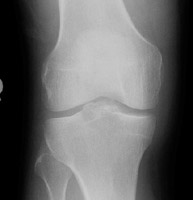

- Click on the image for a larger versionBAP radiograph with slightly different obliquity. This shows irregularity at the region of the tibial spine.